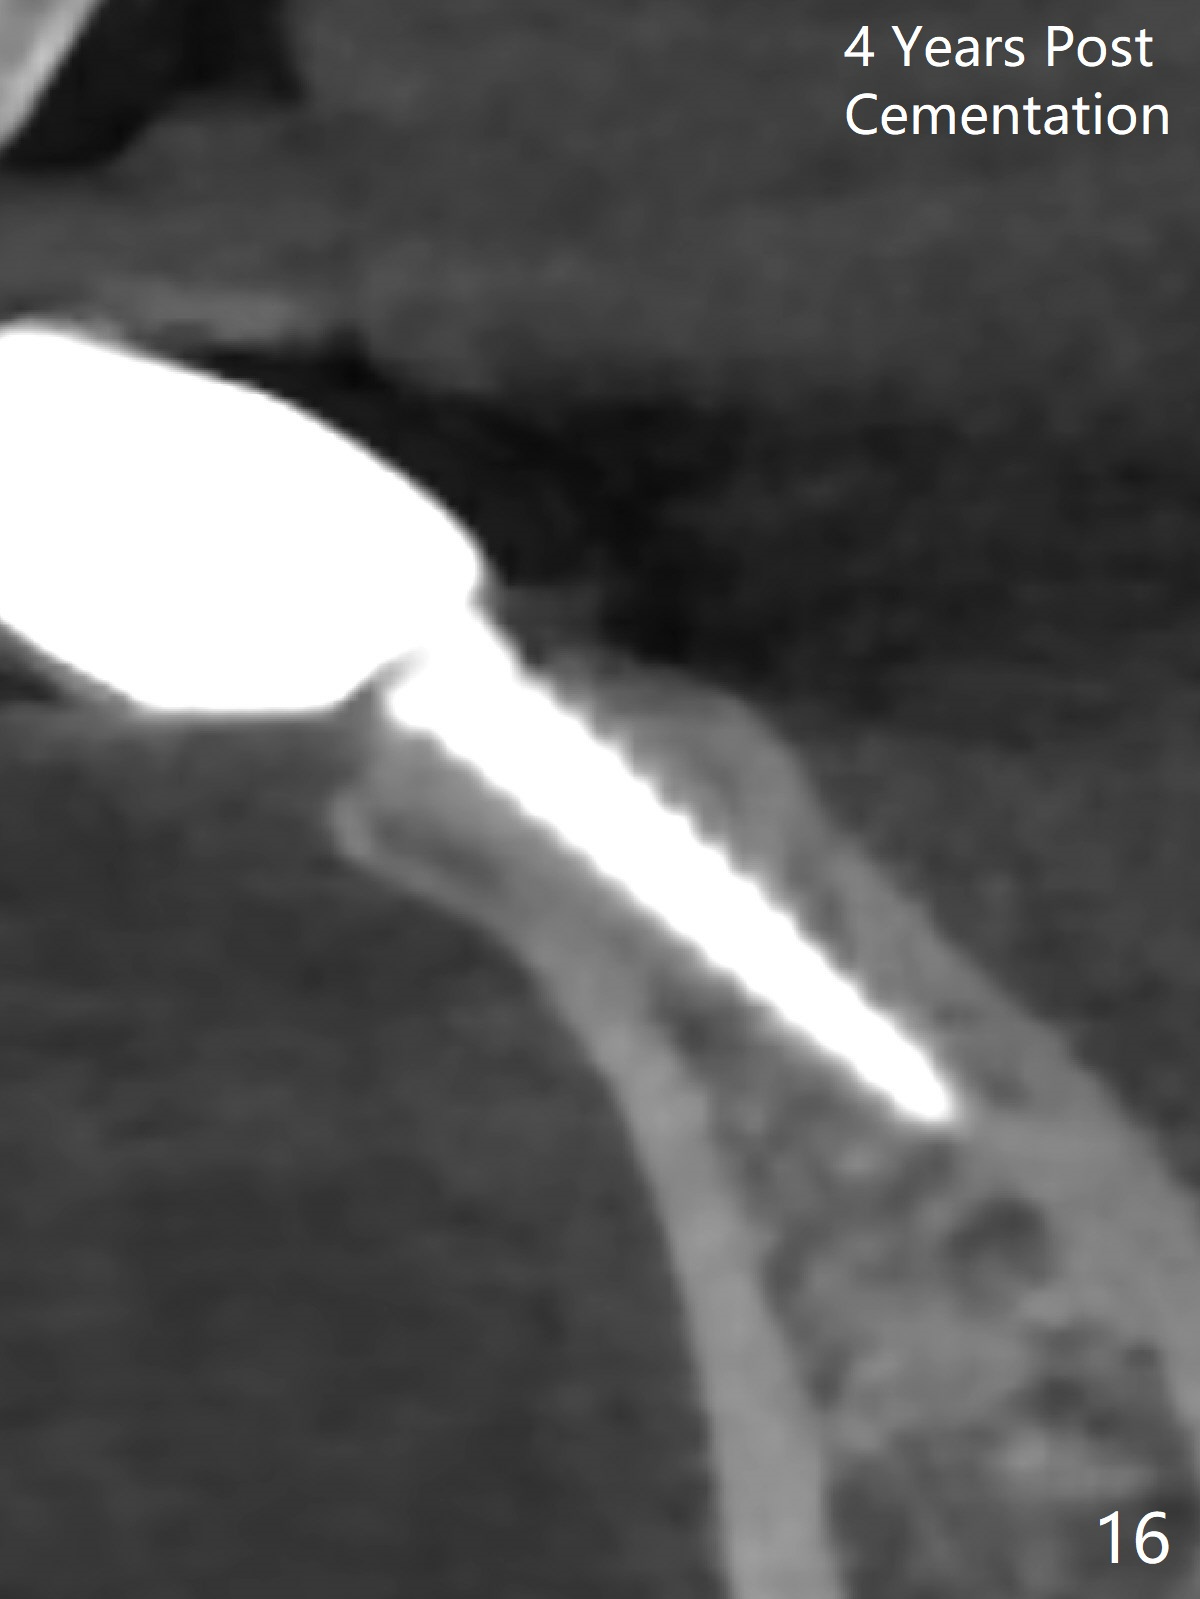

Fig.10,11 show 7 day follow up. The permanent crown is seated 4.5 months postop (Fig.12). Minimal bone resorption occurs at the crest 4 months postop (Fig.13), which is most likely associated with conservative approach (flapless). The patient returns for follow up 2.5 months post cementation (Fig.14,15). The implant remains in the bone 4 years post cementation (Fig.16 CT coronal section; lingual thread exposure, corresponding to preop defect in Fig.1). There is mild coronal bone resorption 5 years 4 months post cementation (Fig.17).